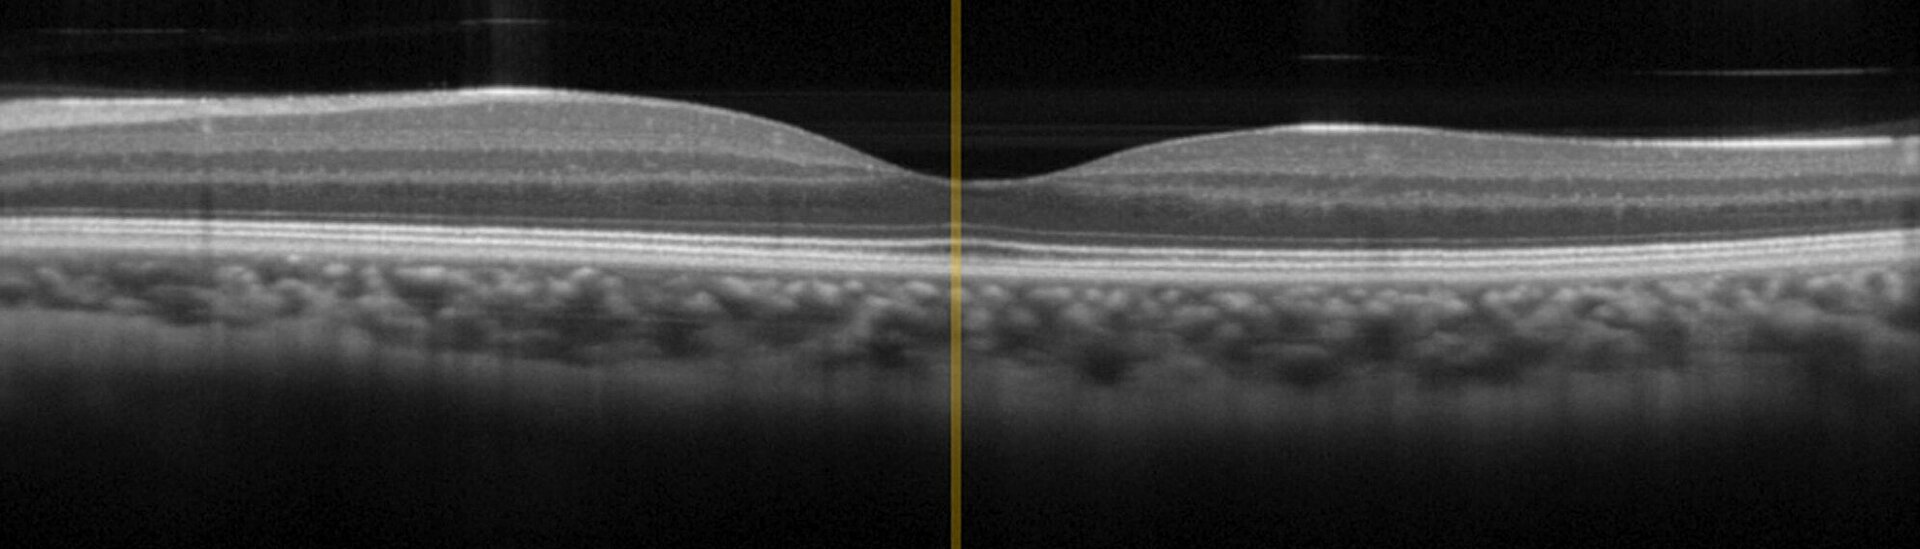

Scanning Stages for Fast and Reliable Image Acquisition in OCT Devices for Ophthalmology and Dermatology

OCT is an interferometric imaging technique based on broadband infrared light in the wavelength range between 0.8 µm and 1.4 µm for optimal tissue penetration. OCT has already achieved "Gold Standard" in ophthalmology but recently also finds growing application in dermatology, for example to diagnose skin cancer. In comparison to conventional invasive diagnostic measures, OCT delivers results faster and reduces side-effects and stress on patients.